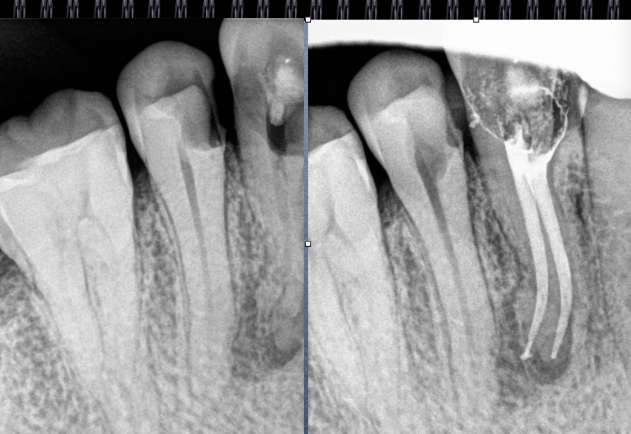

术前片(治疗前知道龋坏的程度,根管的走向)

试尖(检查是否恰填)

根充(从术后X光片可以看出根管充填完整,专业上叫恰充)

根充其实很简单,只要前面的预备做好了,后面的充填就很顺利,试尖恰好,AH树脂湖剂+大准度牙胶充填,平齐根管口将牙胶截掉,冷充的话就结束了。若要做热充,将携热器头对准牙胶的中央,加热3-4秒迅速压入需要截断的部位,然后等十几秒待携热器杆冷却后再加热1-2秒取出牙胶,最后将热牙胶注入,边注边压,严密充填,结束。暂封一周后冠修复。通过这样的操作牙齿就不可能发生再次感染和疼痛了。

常用标准:恰充,三维致密,流畅,锥度流畅一致。

但临床上很难从X-ray上评价一个真正的标准的根管充填。组织学的检验才是金标准。几年的追踪,前后的对比,这些都很重要。 所以我们不能说这个牙我给你做了根管治疗就一辈子没事了,即使你按标准的程序操作,一些复杂的根管系统是我们不能控制的。

临床病例分享: